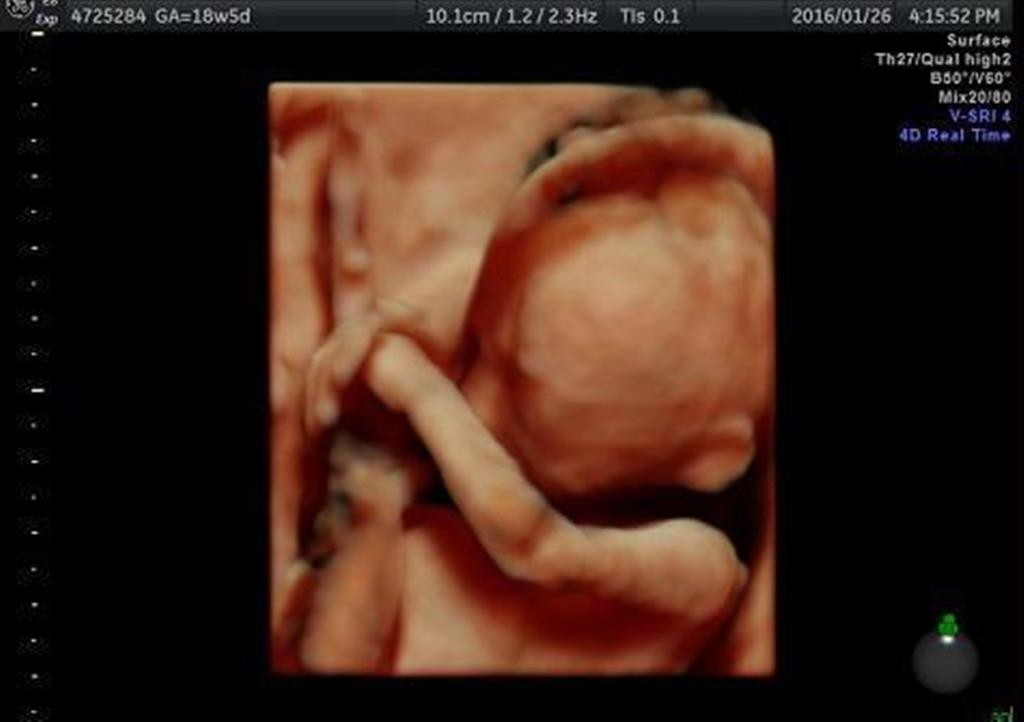

最新の超音波検査機器で撮影された胎児。手の動きなどの様子が鮮明に分かる(ベルランド総合病院提供)